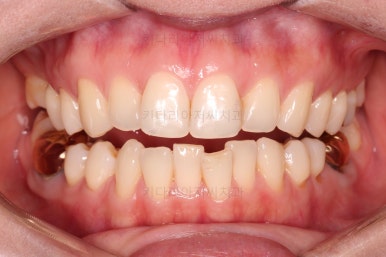

치료 종료시의 모습인데요.

임플란트가 잘 들어갔고 아래 앞니도 원하는 모습으로 잘 배열이 되었습니다.

부산치아교정비용 전후 비교해 볼게요.

치료기간은 임플란트의 안정성 때문에 길어지긴 했으나 사실상 내원횟수는 그리 많지 않으셨고, 교정장치가 눈에 보이는 기간은 7개월정도 밖에 안되었기 때문에 크게 문제되지는 않았던 것 같습니다.

여러 가지가 다 잘 마무리 되었습니다.

이상 아래 앞니 부분교정 및 임플란트를 위한 어금니 부분교정 이후 임플란트까지 완성한 치료사례였고 부산치아교정비용과 가격도 대략 알아보는 시간이었습니다.